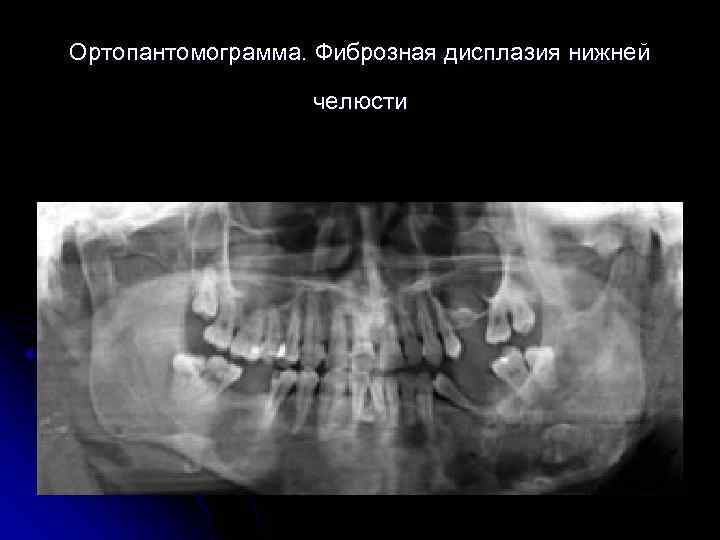

Ортопантомограмма. Фиброзная дисплазия нижней челюсти